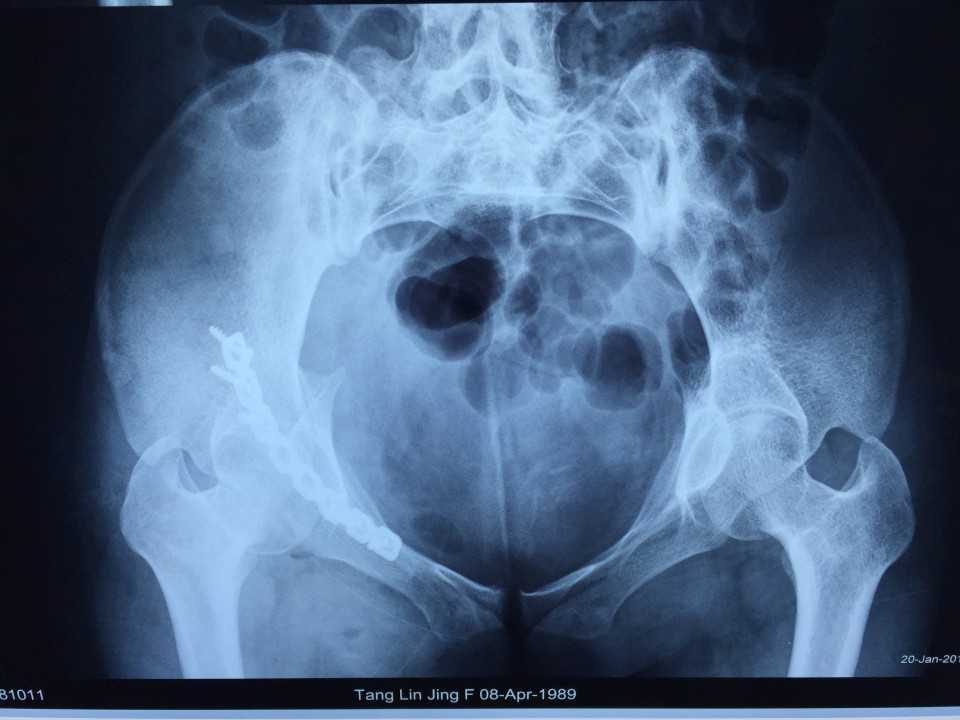

近日,我院创伤骨科七东利用改良Stoppa经腹白线旁入路成功治疗一例髋臼骨折患者。该患者女性,27岁,骨盆车祸伤。术前检查诊断为右侧髋臼骨折(AO分型为A3型)。该患者有剖宫产病史,腹部组织粘黏严重,手术难度较大。经过科室专家多次会诊,刘德宝主任制定详细手术方案,决定术中采用改良Stoppa入路,以减少手术创伤的影响。最终该手术顺利完成,历时一小时余,术中出血仅200ml,术后患者恢复良好。 采用改良Stoppa入路治疗髋臼骨折为安徽省首例,标志着我院创伤骨科进一步迈入创伤省内领先,国内先进的水平。

传统的对于髋臼前壁骨折的治疗方式主要为髂腹股沟入路,此入路内有重要的神经、血管经过,操作费时,术中可能导致股神经、血管及股外侧皮神经、精索或圆韧带的损伤。且骨折需通过3个窗口显露,骨折区域显露有限。针对髂腹股沟入路的缺点,我们使用改良Stoppa入路弥补了髂腹股沟入路的不足,它采用腹白线旁入路,推开腹膜内脏器,腹膜外达到真骨盆缘,一个窗口获得骨盆术野,可很好显露骨盆环。它有以下优点:此入路有宽阔的视野,并能直视骨盆缘,故可有效处理“死亡冠”,减少出血的发生;钢板塑形简单,钢板置入区域真骨盆内缘平坦,只需在一个平面预弯即可,并不需扭转钢板;可双侧骨盆缘复位固定,对于双侧耻骨上支及髋臼前柱骨折可轻易达到;术后病人康复快,因患者经下腹正中入路,并未损伤到髋部周围各层肌肉组织,故患侧肢体术后康复较快。据悉,此项技术在国内仅少数医院开展,在省内尚属首例。